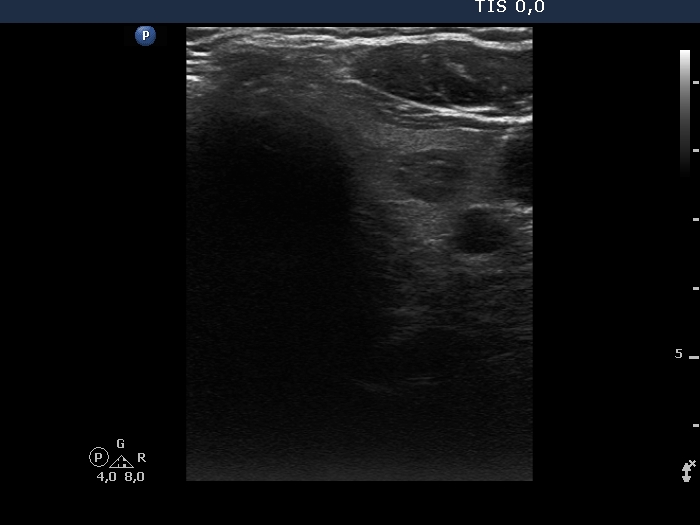

Thyroid cancers - case 1041 (ultrasonographic picture 5)

Left lobe, transverse scan. We did not change the settings, therefore the otherwise normal-size lobe seems to be decreased. There is a hypoechoic nodule in the central part.